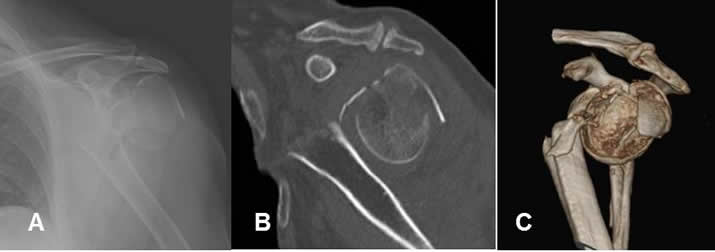

Fig 142 A. Luxofractura de hombro en reconstrucción 3 D.

A: Rx AP, B: TAC reconstrucción sagital y C: TAC reconstrucción 3 D. Luxofractura del hombro, con gran desplazamiento y angulación de la cabeza del húmero. Por las características de esta lesión, se debe descartar compromiso vascular.